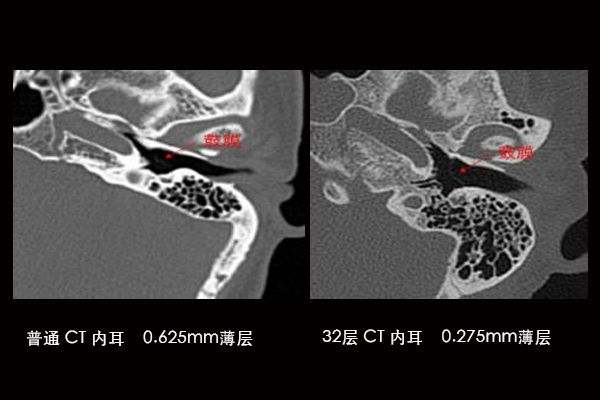

内耳

微视距扫描技术

世界独有专利 “0.275”薄层扫描技术。 目前世界上最薄的扫描层厚只能做到0.5mm,而层厚越薄,对比分辨率越高,看到的细节也越清晰,该32层CT做到了目前极致的 0.275mm 超薄层厚扫描

内耳检查

内耳畸形

如Mondini畸形(耳蜗发育不全)、大前庭导水管综合征等,是儿童感音神经性聋的重要病因。CT可明确畸形类型,为人工耳蜗植入提供关键解剖依据

胆脂瘤或中耳炎累及内耳

慢性中耳炎或胆脂瘤可能侵蚀内耳结构,导致眩晕、听力骤降。CT能判断骨质破坏范围,评估是否出现瘘管(如半规管瘘

颞骨骨折

头部外伤后,横行骨折易损伤耳蜗、前庭,导致感音神经性聋。CT是诊断骨折线走向及内耳受累的金标准

听神经瘤等占位性病变

虽MRI更优,但CT可显示内听道是否扩大、骨壁是否破坏,作为初步筛查手段